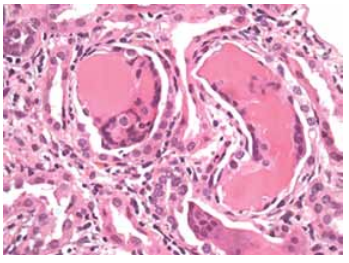

Mulher de 65 anos, hipertensa, foi avaliada para dorsalgia torácica, injúria renal aguda, anemia e hipercalcemia. A paciente usava ibuprofeno 3-4 vezes/dia, losartana e clortalidona. O exame de urina mostrou traços de proteína, e a relação proteína-creatinina na urina foi de 4,8 mg/mg. As cadeias leves λ livres de soro foram de 726 mg/dL, e a relação κ/λ foi de 0,3. Apesar da hidratação intravenosa e da correção da hipercalcemia, sua função renal piorou, e foi iniciada hemodiálise e realizada uma biópsia renal.

(Hematoxilina e eosina; aumento original, ×400.Disponível em: https://www.ajkd.org)

Qual achado de biópsia renal provavelmente será observado nesta paciente?